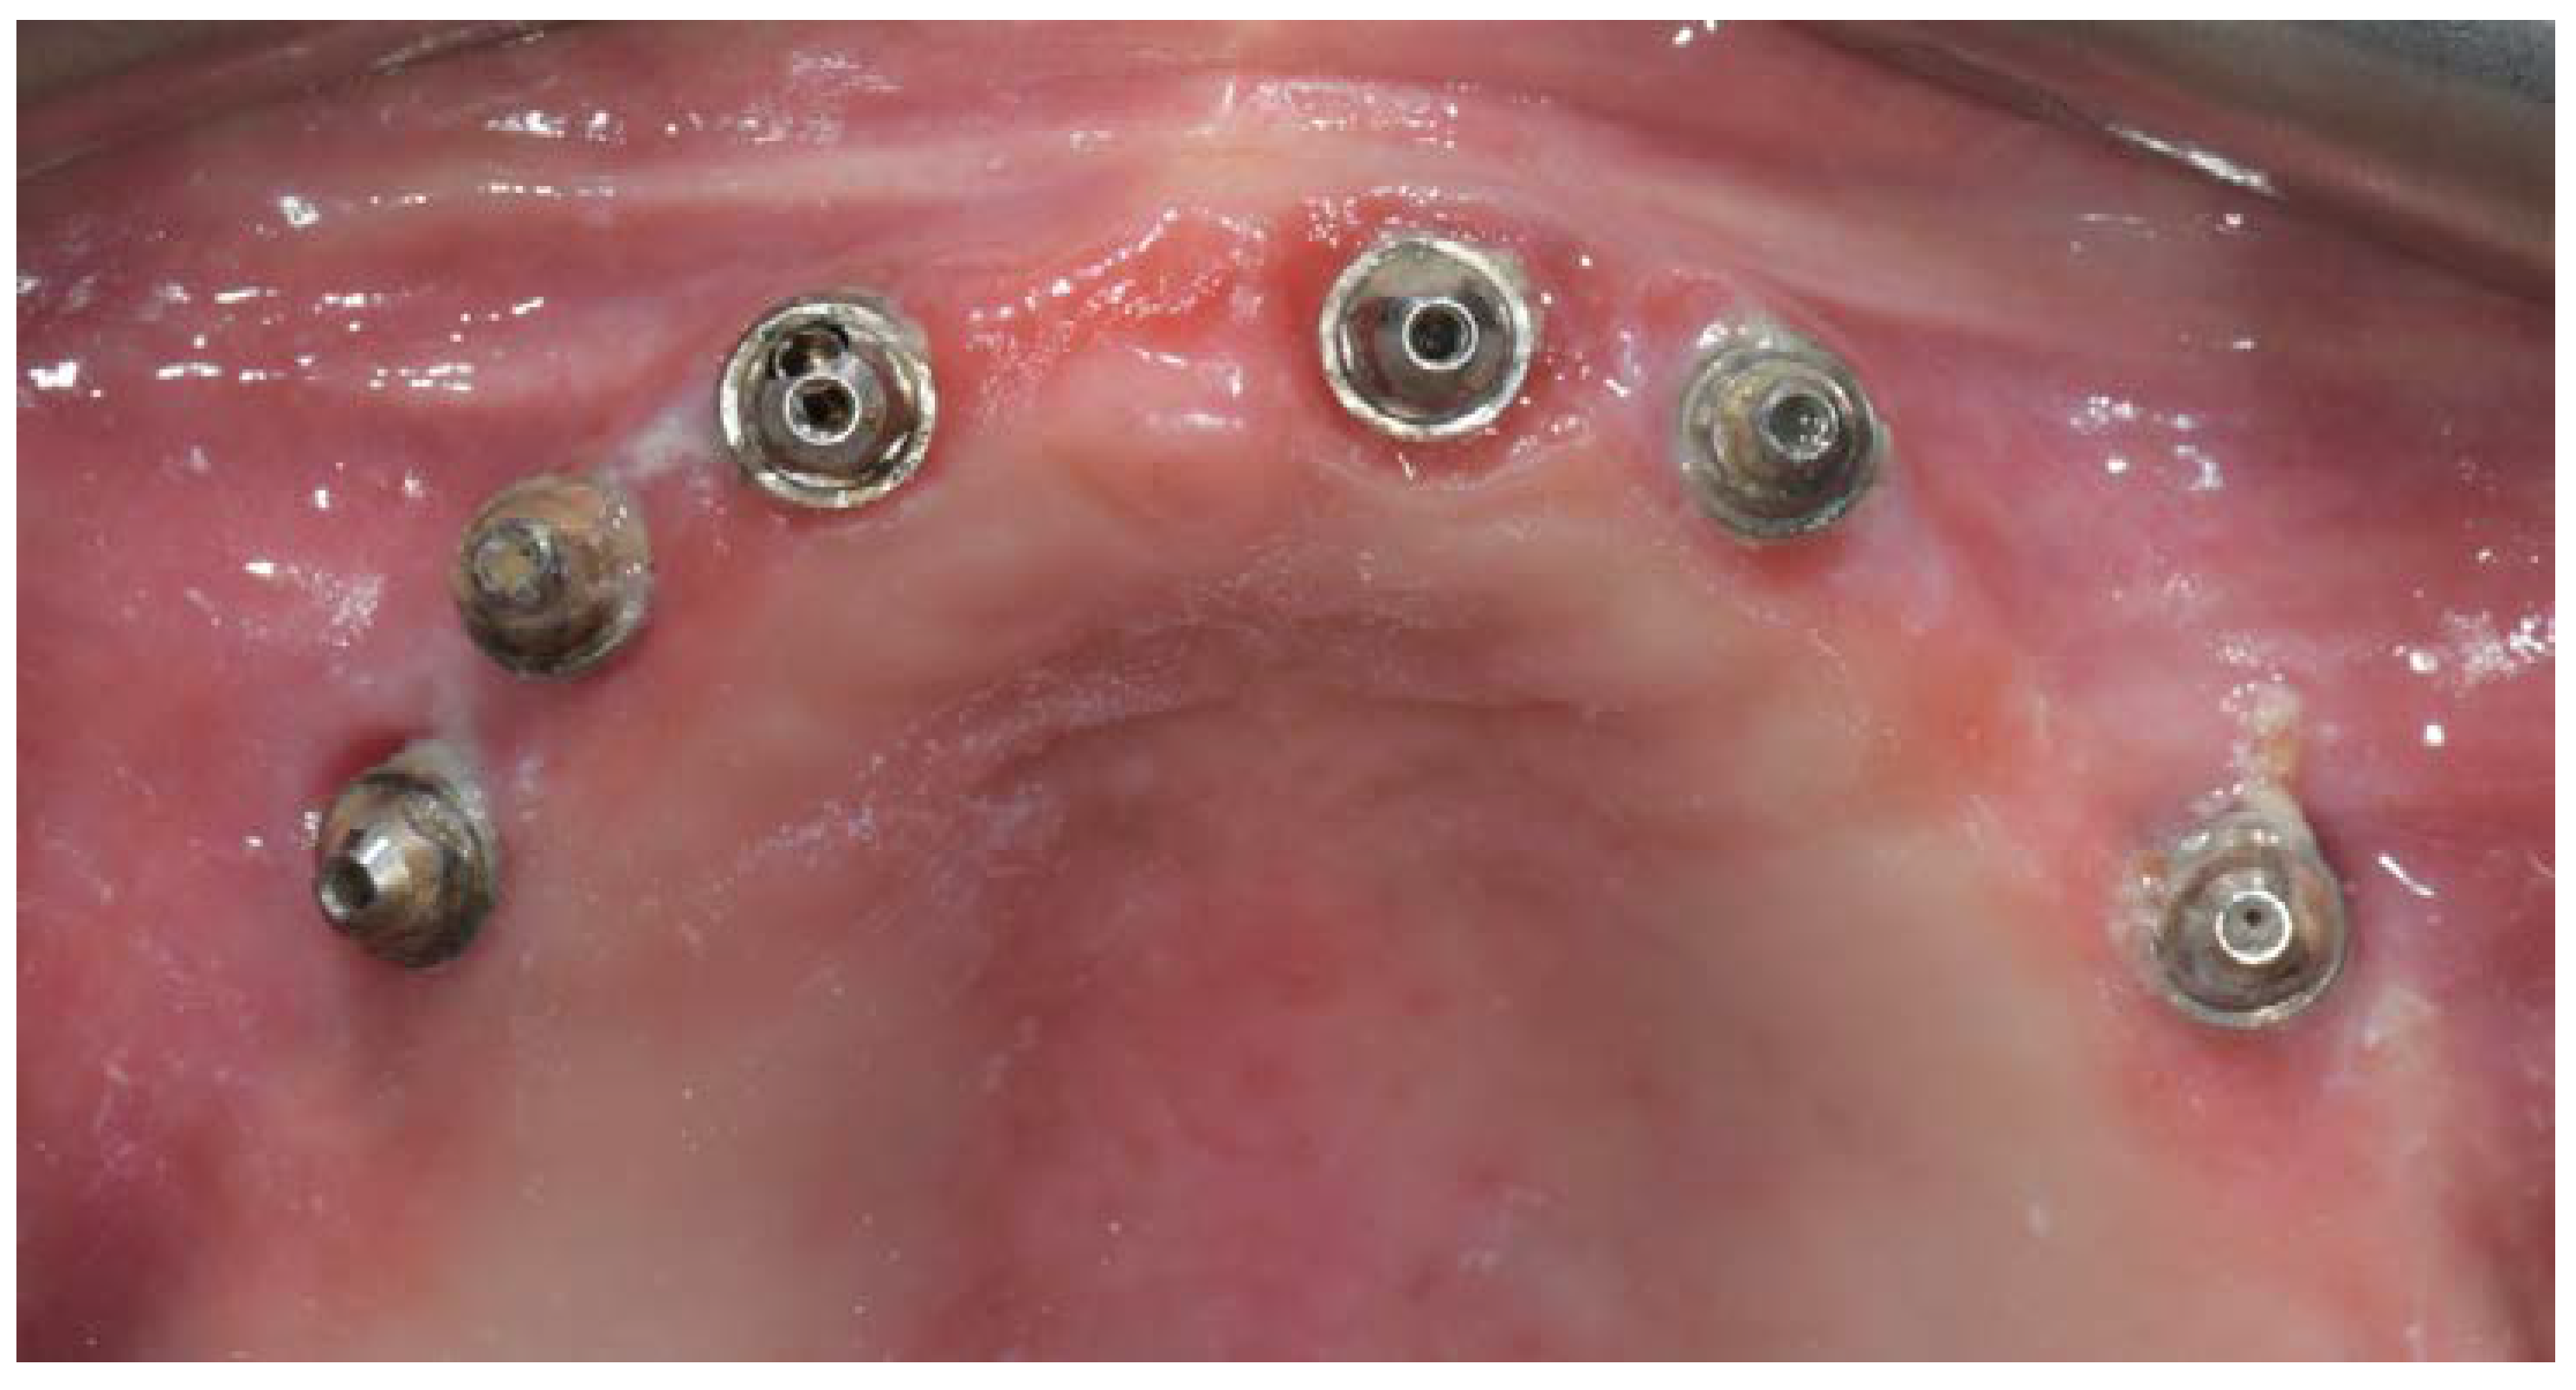

A partially edentulous 78-year-old woman with a complete screw-retained implant-support hybrid prosthesis (Figure 1) in the upper jaw and natural dentition in the lower jaw was referred to a private center in Rome, Italy, due to several continuous breakages of the prosthetic part of the implant-supported rehabilitation. After a preliminary interview, the patient stated that the implant treatment was finished two years before, but she had never been comfortable with this prosthesis (Figure 2). Relevant symptoms were phonetic difficulties, inability to maintain hygiene, and repeated breakages, leading to functional and esthetic issues (Figure 3). After that, the patient’s medical history was collected, and preoperative photographs, radiographs, periodontal screening results, and model casts were obtained for initial evaluation (Figure 4). During the clinical examination, the actual prosthesis was unscrewed, due to teeth detachments, and replaced with the old temporary prosthesis delivered by the patient. Both existing prostheses were evaluated and judged inaccurate, with particular attention to the fit of the prosthesis, the vertical dimension of occlusion, phonetics, facial support, and lip position. All the possible treatment options were then discussed and evaluated together with the patient. The main concerns of maintaining the previously placed implants were some exposed threads and the troubling disparallelism that makes the prosthetic treatment difficult, increasing the risk for biological complications and technical complications, respectively (Figure 5). Nevertheless, the patient refused a complete removable denture, so that implant removal would lead to placement of new implants, in combination with guided bone reconstruction and soft tissue management. This treatment plan may have the risks of implant failure and increased patient morbidity (Table 1 and Table 2). An implant-supported fixed dental prosthesis was initially excluded due to the implant’s disparallelism. Hence, a maxillary implant-supported overdenture was initially considered quite possibly the best therapeutic option.

Figure 5.

Intraoral picture of the implant positions and the multi-unit abutment screwed on.

Before definitive impression, multi-unit abutments were unscrewed, the implant connections were cleaned, and six OT Equator Titanium Abutments (Rhein’83, Bologna, Italy) with TiN coating were screwed (Figure 6), according to the manufacturer. Immediately after, the patient received a digital impression (CS 3600 intraoral scanner, Carestream Dental, Milan, Italy), taken at abutment level (Figure 7), using dedicated scan abutments (OT Equator Titanium Scan Abutment, Rhein’83). However, overlapping of the captured images failed to produce an accurate impression, maybe due to the disparallelism of the implant ranging from 65° to 86°. Hence, a prototype model was created and a convention gypsum impression [16] with a customized impression tray was taken at abutment level using conventional impression coping (Titanium Impression Coping, Rhein’83; Figure 8 and Figure 9). Esthetics, phonetics, the occlusal vertical dimension, and the centric relation were verified and approved by both the clinician and the patient (Figure 10 and Figure 11). Only after that, a definitive cast, implant position, and esthetic try-in were digitalized and a CAD/CAM titanium bar (NewAncorvis, Bologna, Italy) was anatomically designed with a dedicated software (Exocad DentalCAD, Exocad, Darmstadt, Germany) by a certified dental technician (MA), according to the prosthetic contours and the implant position. Three projects were created with a three-, two-, or one-piece CAD/CAM titanium bar, respectively (Figure 11b). Each of these projects failed to create an accurate titanium bar able to respect the minimum restorative space required by the prosthetic volume of the tried prosthesis, due to the multiple components involved (attachment system, prosthetic framework, artificial acrylic composite teeth, and pink acrylic base). Hence, a fourth project was created with a CAD/CAM titanium bar designed for a fixed screw-retained restoration, initially excluded due to the implant disparallelism. In order to overcome the undercuts created by the tilted implants, and to produce a passive-fit CAD/CAM titanium bar, abutments with an extragrade system were applied (Figure 11c). Extragrade is a special titanium abutment which has the possibility of entering, even in cases of strong disparallelisms, thanks to its internal design. On a large number of implants (those positioned worse from the point of view of the emergence profile), we cannot put the through screw. In this case, the abutment will be retained by the white Seeger only. The number of abutments without screws was limited to two, according to the manufacturer and considering the overall number of placed implants. Moreover, an angulated screw channel concept was applied to avoid the access hole in the vestibular area of the anterior teeth, moving the access holes in the pink area of the hybrid prosthesis. The fit of the implant bar was clinically and radiographically tested in the patient’s mouth, according to established criteria ([17,18,19]; Figure 12). It was important to position the flat surfaces of the abutment-bar connections in correspondence with the undercut created by the inclination of the implant; the flat surface indicates the location of the extragrade bevel, which allows the framework to overcome the undercuts created by the tilted implants. After that, an interocclusal record was taken in centric relation, and the prosthesis was delivered. The screw-retained fixed complete implant-supported prosthesis was seated in the patient’s mouth using the snap-on function offered served by the Seeger System (Figure 13). Four out of six screws were tightened according to the manufacturer, and the screw-holes were closed using composite pink materials. Finally, the occlusion was adjusted and radiographs were taken. The patient was scheduled for hygiene maintenance and control every 4 months (Figure 14, Figure 15 and Figure 16).